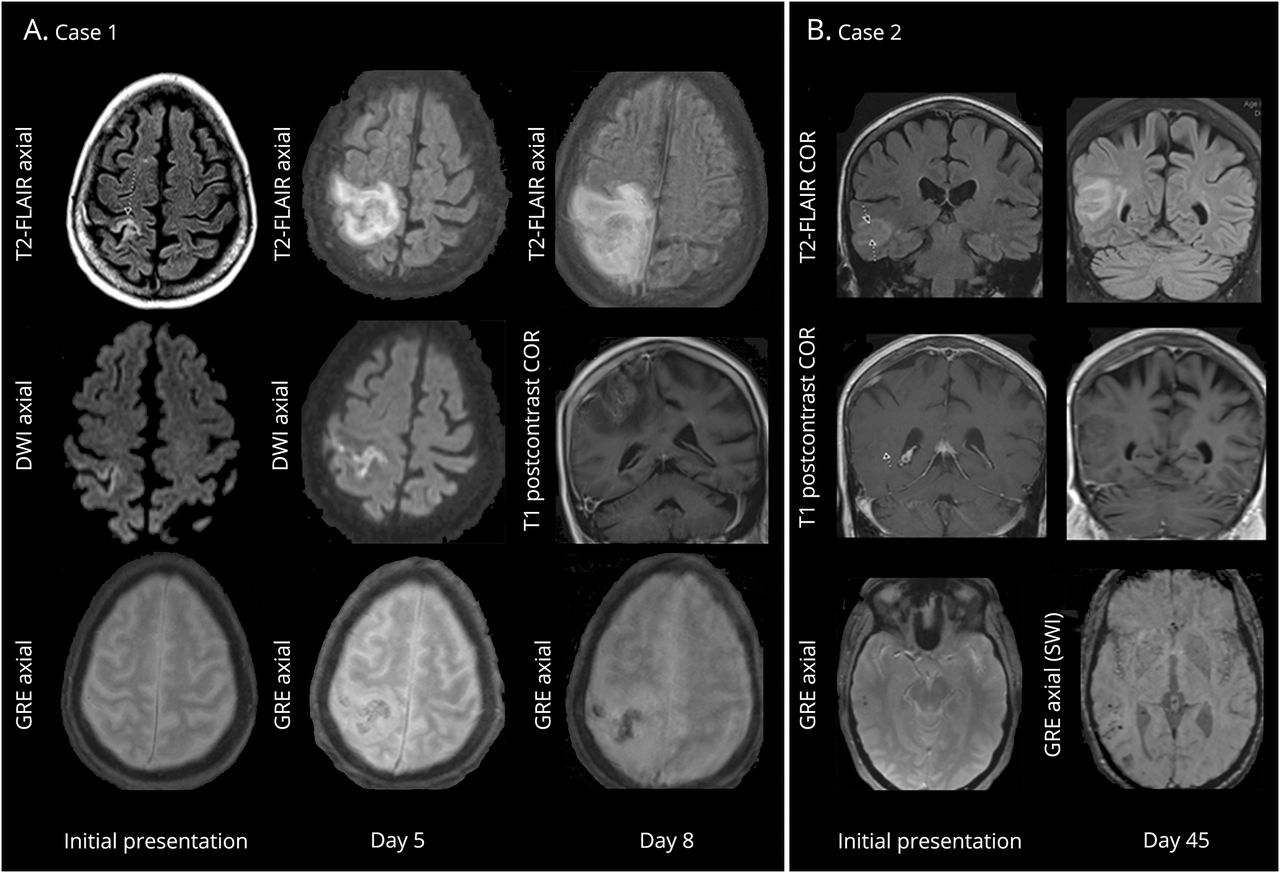

(一)案例1:上面一行:发展高T2 / fluid-attenuated反转恢复(天赋)信号/右额-顶叶水肿;中间行:温和对frontoparietal皮质基于扩散限制,微弱的正确frontoparietal旋转的增强;底下一行:进步的易感性工件(出血)梯度地区的成像信号异常。(B)案例2:上面一行:进步的高T2 /天赋信号/水肿右颞顶叶;中间行:非常微弱leptomeningeal增强区域水肿;底下一行:基于渐进皮质易感性工件(出血)地区的水肿。

连续视频脑电图监测演示了一个由癫痫引起的关注正确的中部地区和levetiracetam就开始了。基于大脑MRI没有对比显示一个线性,皮质对frontoparietal不清楚病因病变(图1一个)。重复gadolinium-enhanced磁共振成像(图1一个)显示似的质量恶化的皮质gyra肿胀和中央前和中央后旋转的水肿而增强。第八天,成像显示增加肿胀后右额叶脑回,前右顶叶与周边水肿、出血,和当地质量效应(图1一个)。CT血管造影术的头部并没有暗示血管病变或动脉瘤。临床上,病人继续演示间歇性左弱点。鉴别诊断包括传染性脑炎、简单的局部癫痫持续状态,辅助影像学异常,血管炎,或化疗毒性。脑转移被认为是由于似的质量扩张(图1一个),但被认为是不太可能由于缺乏对比度增强。

影像学发现典型的转移。基于成像显示皮质病变缺乏典型的增强模式转移。在第一种情况下,扩散限制的线性模式集中在右frontoparietal皮层最初怀疑脑炎。2,神经胶质瘤被认为是由于离散似的质量性质的病变与周围水肿。这种病变没有展示典型的对比度增强的乳腺癌转移和非典型位置,微弱的leptomeningeal增强,敏感构件梯度回波序列不符合主神经胶质瘤的经典模式。在这两种情况下,成像特点是不足以建立一个诊断和进一步调查与活检是必要的。